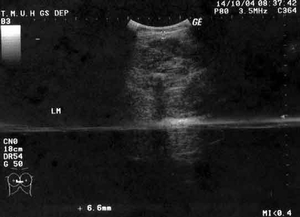

超音波: 追蹤小腿抽脂後的情況--- 上圖消費者皮下脂肪術後剩下6.6毫米(mm).